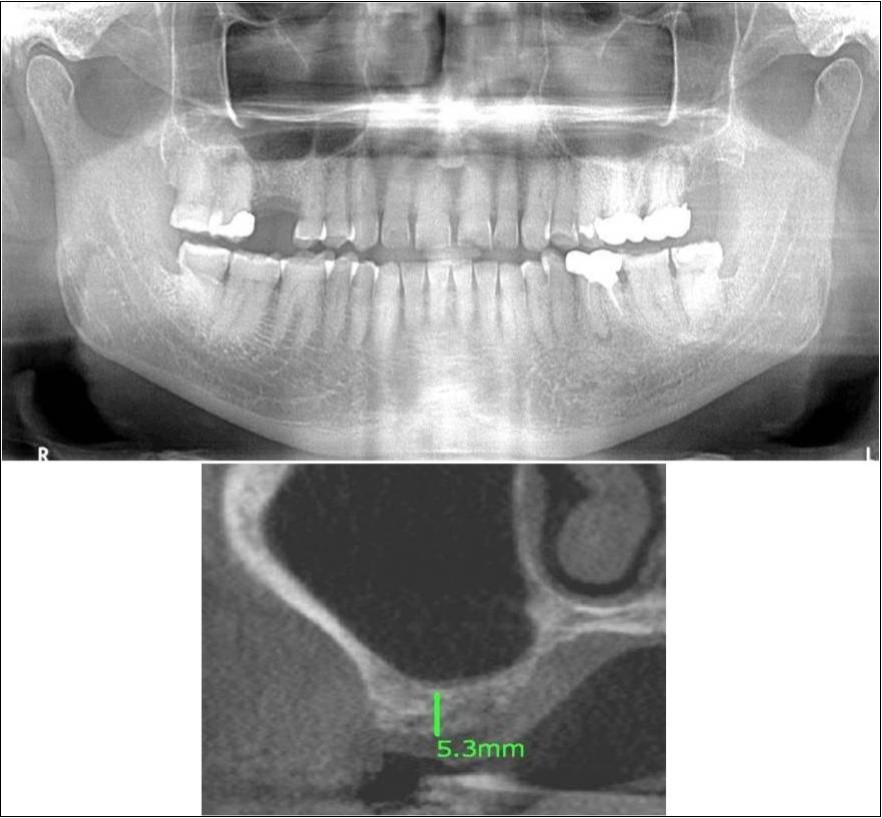

Clinical and Radiological Assessment:

1.Partially edentulous maxillary arch with missing 16;

2.Increased pneumatisation of right maxillary sinus;

3.Height of available bone- 5.3mm;

4.Transverse thickness of available bone (CBCT evaluation)- 10.2mm;

5.Inter-ridge space adequate to place implant (10mm).

Treatment:

Patient underwent the procedure of indirect sinus elevation using sinus osteotomes in relation to 16 region. Calcium phosphosilicate putty was dispensed as the graft material through the crestal osteotomy site to maintain the elevated sinus membrane followed by placement of a dental implant measuring 5 x 10mm under local anaesthesia and strict aseptic protocols. The implant was allowed to osseo-integrate for a period of six months during which the patient was followed-up periodically and was assessed for peri-implantitis, crestal bone loss and mobility. At the end of 6 months, a repeat CBCT scan was advised to evaluate the increase in bone height. (Figure 11a,b, pre-treatment; Figure 12a,b, post-treatment)

Figure 11.(a,b) Pre-treatment OPG and cross section of CBCT showing residual alveolar bone height for Case No.3

Figure 12.(a,b) Post-treatment OPG and cross section of CBCT showing residual alveolar bone height for Case No.3;